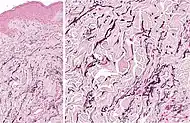

| Actinic elastosis (most common, also called solar elastosis) |

Elastin replacing collagen fibers of the papillary dermis and reticular dermis |  |

| Perforating calcific elastosis | Clumping of short elastic fibers in the dermis.[11] |  |

| Linear focal elastosis | Accumulation of fragmented elastotic material within the papillary dermis and transcutaneous elimination of elastotic fibers.[11] |  |